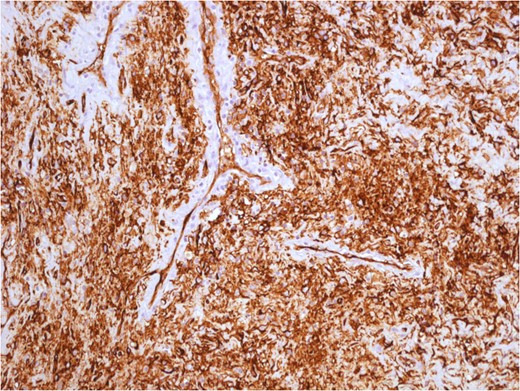

Surgical treatment was carried out with a posterior approach (Fig. 5). The lesion was in close proximity of elevator ani muscle and lateral rectal wall, that were not macroscopically infiltrated. The lesion area was marked with surgical clips because of the close proximity with rectal wall, for eventual post-operative chemotherapy or radiotherapy and for follow-up. Surgical specimen was an oval, soft tissue mass of 11 × 7.5 × 5.5 cm in size, capsulated, hyper-vascularized, with a inhomogeneous aspect, multi-lobed (Fig. 6). Microscopically, the tumour was composed by a proliferation of spindle cells crossed by stromal collagen and giant plurinucleate cells. Neoplastic cells immunophenotype showed expression for CD34 and bcl-2 (Figs 7–9).

Variable cellularity and vascular patterns hemangiopericitoma-like in solitary fibrous tumour.

Uniform spindled cells in variably collagenous and vascular pattern. The tumour cells form random and trabecular arrangements.

The tumour cells have indistinct cytoplasm and oval nuclei, with inconspicuous nucleoli. Collagenous background is evident. Mitotic activity is absent. SPT cells are positive for BCL2 and CD34.

The histological appearance of SFTs may overlap with other benign and malignant diagnostic entities, such as hemangiopericytoma, leiomyoma, nodular fasciitis, inflammatory myofibroblastic tumour, fibromatosis and benign peripheral nerve sheet tumour [5]. In the past, SFTs were considered rare tumours originated from mesothelial cells. This has been recently proved using immunohistochemical analysis, particularly positive staining for CD34 and bcl-2 is an indication of SFT [5]. Usually, microscopic features are the presence of relatively spindled cell set in variably collagenous, cellular and in some cases myxoid matrix. An hemangiopericitoma-like vascular pattern in seen at least focally in most cases. Tumour cells have indistinct cytoplasm and oval nuclei, with inconspicuous nucleoli. Mitotic activity is low (<2–3 mitoses/10 HPF, high-power fields) in most cases, but some tumours show overtly sarcomatous features with a high mitotic activity.